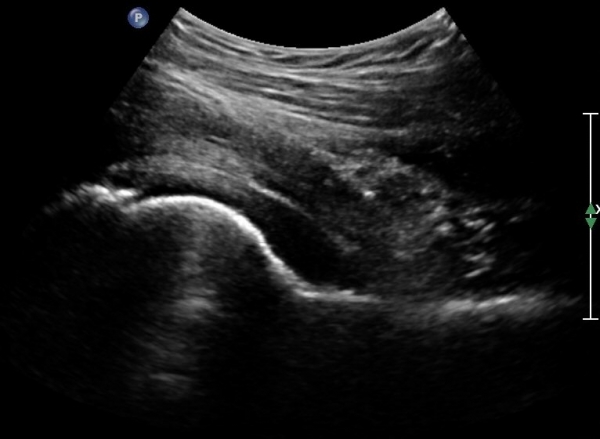

[¾ûµ¢ÀÌ] °í°üÀý Ãæµ¹ÁõÈıº¿¡ÀÇÇÑ È°¾×¸·¿° ÁÖ»çÄ¡·á